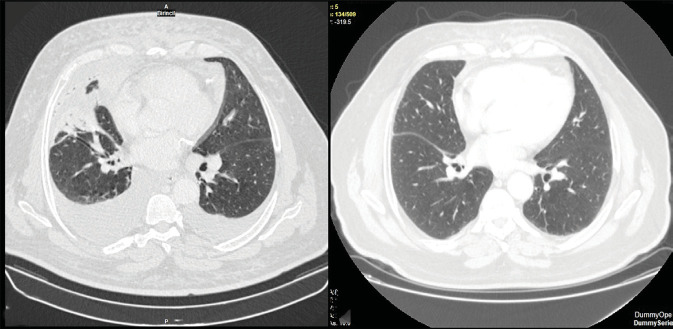

Mycosis fungoides is the most commonly seen type of cutaneous T-cell lymphoproliferative disease. While mycosis fungoides is linked to an increased risk of developing secondary malignancies, the occurrence of B-cell-originated disease in association with it is exceedingly rare. A 66-year-old male with persistent papillomatous skin eruption was admitted due to dyspnea. Chest X-ray, positron emission tomography, and chest computed tomography revealed axillary and mediastinal lymph node enlargement and right lower pulmonary lobe infiltration along with right-sided massive pleural effusion. Histological and immunohistochemical findings of pleural biopsy and axillary lymph nodes suggested a diagnosis of pulmonary extranodal marginal zone lymphoma. Skin biopsies from the abdomen, chest, and legs revealed CD4/CD8 double-positive patch stage of mycosis fungoides. After completing six cycles of chemotherapy, complete remission of lymphoma was achieved, with the skin eruptions remaining unchanged. Herein, the authors present a unique case of concomitant diagnoses of mycosis fungoides and marginal zone B-cell lymphoma of the respiratory system to emphasize the importance of careful evaluation of each finding.